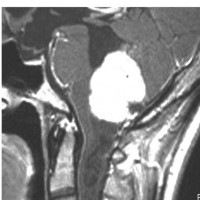

類表皮のう胞 epidermoid cyst

脳幹部に食い込むようにして増大した第4脳室の類表皮のう胞です。右側の画像は拡散強調画像 DWIです。これで高信号(白く)にみえるのが特徴です。

脊髄空洞症 syringomyeliaの合併

上と同じ患者さんです。大後頭孔での髄液流が悪くなるため,また腫瘍が何年もかかってゆっくり大きくなるので,脊髄に空洞ができました(脊髄空洞症)。脊髄の内部が裂けてしまうので,強い胸部の疼痛がでて発症しました。

第4脳室腫瘍を摘出するとこの空洞症は自然に治るので,何もしません。また症状も良くなることが多いです。